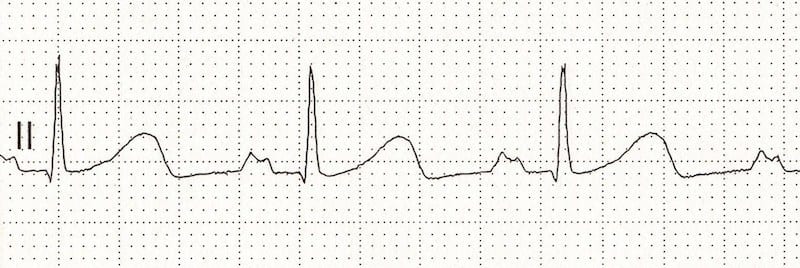

ECG Example – U Wave

Note that there is a positive deflection (arrowed) after the T wave, and before the next P wave, that is the U wave.

© Life in the Fast Lane. Licensed under CC BY-NC 4.0